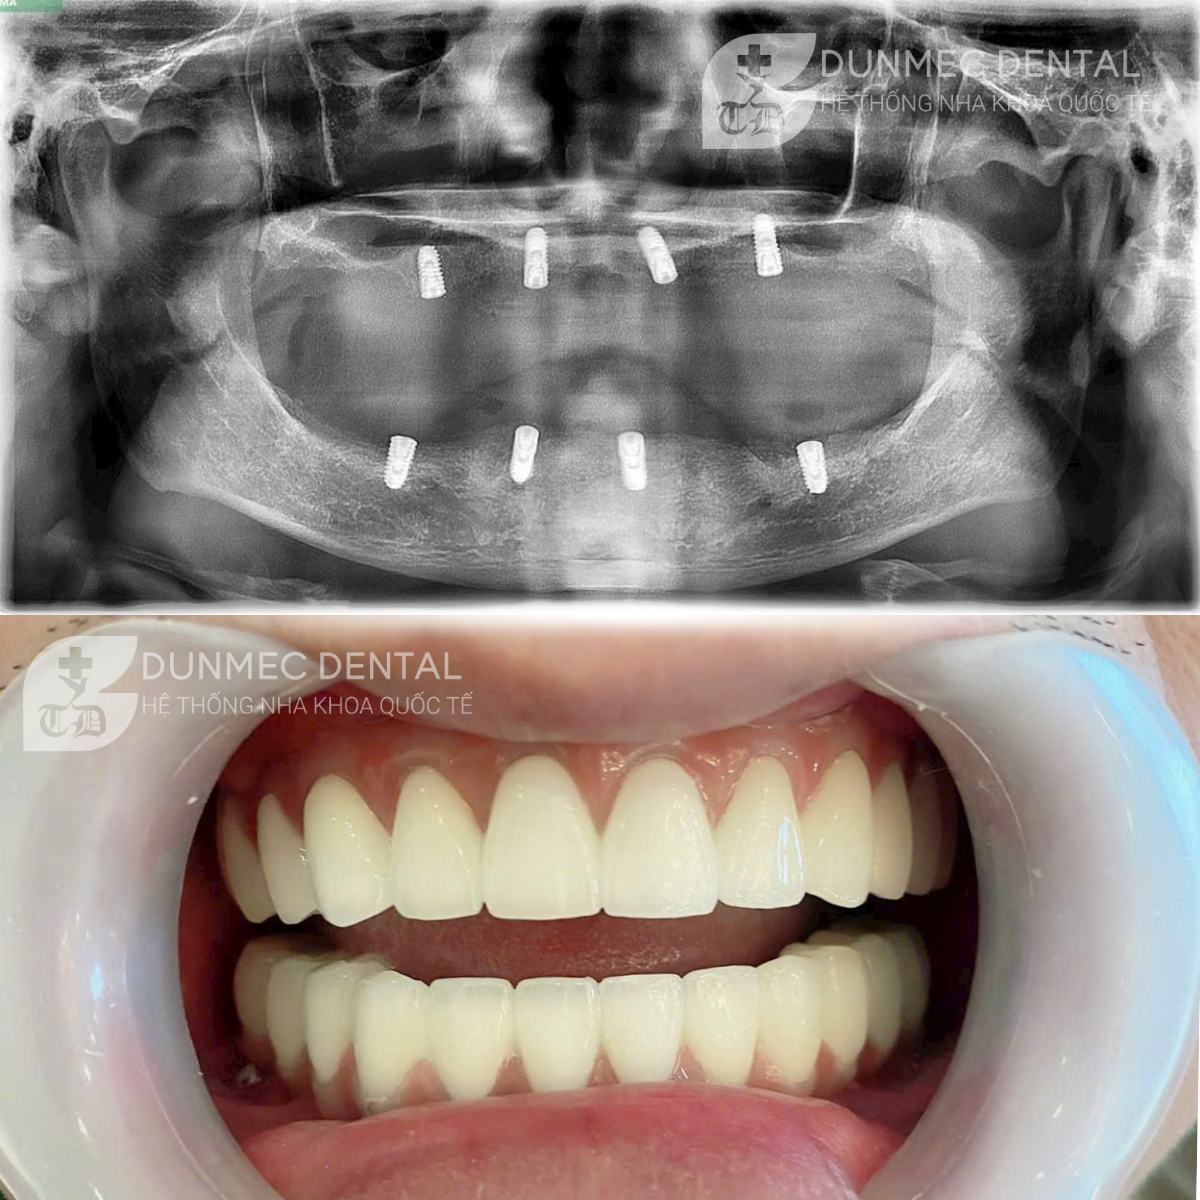

SỰ KHÁC BIỆT TẠO NÊN UY TÍN DUNMEC Dental

4 khác biệt tạo nên Nha DUNMEC uy tín chất lượng Trong những năm qua Nha Khoa DUNMEC là địa chỉ chăm sóc răng miệng uy tín, phục vụ cho hàng triệu khách hàng trên khắp Việt Nam. Vậy đâu là những đặ...

Trẻ hóa nhan sắc với nụ cười thiết kế tỷ lệ chuẩn đẹp từ Dunmec dental Tại dunmec, ngoài công nghệ hiện đại, chất lượng răng sứ đạt chuẩn châu Âu thì một điểm mấu chốt làm nên những tuyệt tác nụ cư...